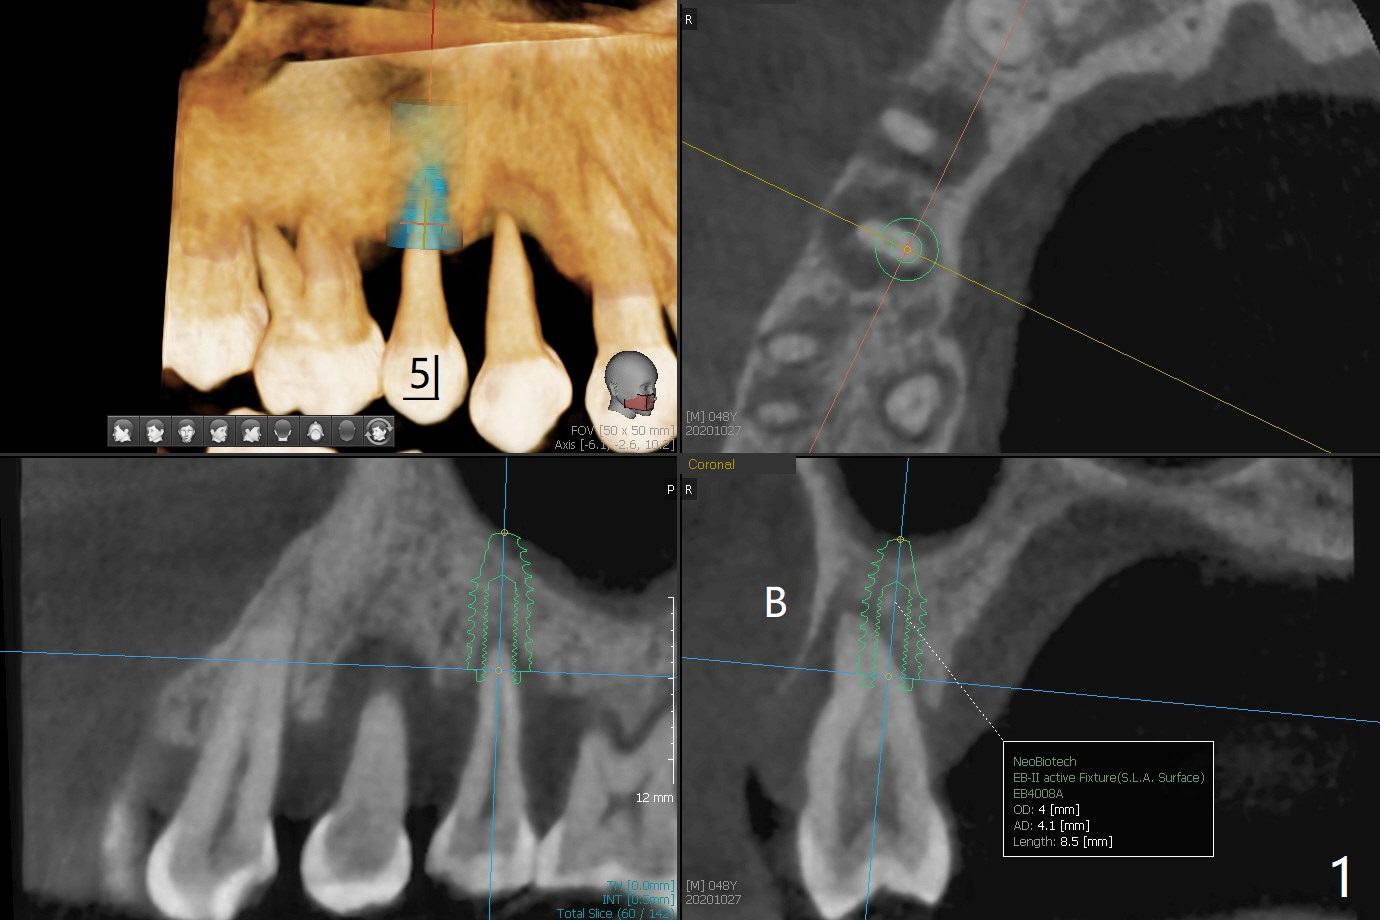

术前CT显示右上4牙槽骨比5窄(图一,二),3.5毫米植体比较合适,况且牙龈厚,基台长的一段式植体显得得当。为了取得最好的植体方位,4先拔除(图三),种植(图四),调整后者深度后,拔除5(术前征求病人同意),开始钻洞(图五),完成种植(图六)。粘性骨粉不仅放置于植体周围,而且6牙根近中(图七),4/5牙槽嵴和龈乳头(P)之间,减少术后龈乳头萎缩(图八:*)。制作两个分开临时牙冠,有利于维持龈乳头。对于病人来说,临时牙冠帮助咀嚼,而对侧拔牙创无法吃饭。术后3个月两个分开临时牙冠(其中一个龈方移位(图九:箭头)保持龈乳头(*)和牙龈外形(图十:*)。临时牙冠取出后,调整基台高度,少量钛屑(不妨大局)附着在健康的牙龈沟(图十一),再次显示两个基台之间龈乳头(图十二:*),衬里,修整的临时牙冠又插回牙龈沟(图十三:箭头),继续维持软组织形态,准备一个月后,调整基台边缘(图十二:箭头),取模。术后五个月大部分骨粉依然保留在植体和邻牙周围,龈乳头退缩不多(图十四: P)。三个月后(术后六个月)钛削无影无踪(图十五,与图十一对比))。永久性牙冠周围空间慢慢会消失(图十六,使用临时性胶水)。